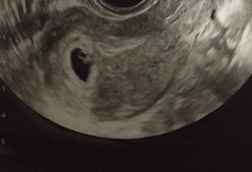

Ragazze chi ci prova ??Metodo Ramzi! Chi ci sa azzeccare? 4

• Rispondi